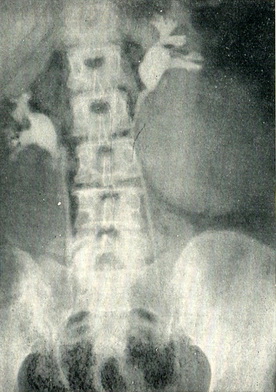

На оглядовій рентгенограмі часто виходять тіні нирок, що дозволяє встановити збільшені і неправильні контури нирки, ураженої пухлиною. Вирішальне значення має ретроградна пієлографія. Якщо пухлина проростає або здавлює ниркові келихи, на ретроградної пиелограмме видно відповідні зміни їх (рис. 101 і 102). Якщо пухлина проросла в ниркову балію, виявляється дефект наповнення. Контрастна речовина може зовсім не проникнути в балію, якщо пухлина проросла заповнює її порожнину. Пухлини, що походять з нижнього полюса, часто відтісняють верхній відрізок сечоводу в сторону хребта у вигляді дуги, зверненої опуклістю в медіальну сторону (див. рис. 102). Важливим симптомом є асиметричне розташування ниркової миски по відношенню до нирці. При пухлини, витікаючої з полюса нирки, балія зміщується до протилежного полюса (рис. 103).

Рис. 101. Пухлина лівої нирки, що виходить з нижнелатерального краю її. Нижня і середня чашечки здавлені і відсунуті один від одного. Ретроградна пієлограма.